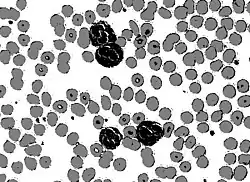

Original image: neutrophil white blood cells (leukocytes)

Circular thresholding is an algorithm for automatic image threshold selection in image processing. Most threshold selection algorithms assume that the values (e.g. intensities) lie on a linear scale. However, some quantities such as hue and orientation are a circular quantity, and therefore require circular thresholding algorithms. The example shows that the standard linear version of Otsu's method when applied to the hue channel of an image of blood cells fails to correctly segment the large white blood cells (leukocytes). In contrast the white blood cells are correctly segmented by the circular version of Otsu's method.